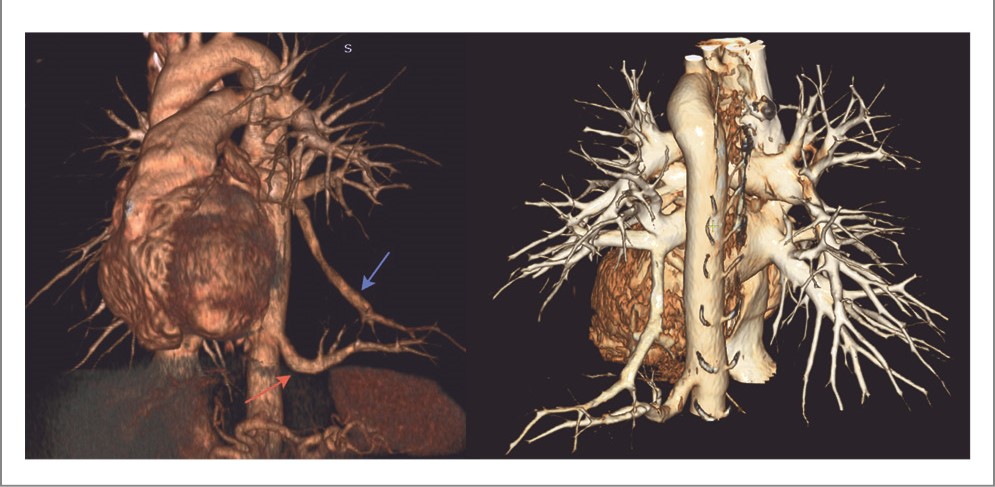

При МСКТ-ангиографии данное образование имеет автономное кровоснабжение от грудного отдела аорты диаметром до 0,88 см на уровне Th11 позвонка. Венозный отток осуществляется через ветвь нижней легочной вены диаметром до 0,77 см непосредственно в левое предсердие (рис. 3).

Рис. 3. МСКТ-ангиография ОГК в аксиальной и фронтальной проекции: a – на уровне Th11 позвонка слева отходит крупная ветвь из грудного отдела аорты – аберрантная артерия; b – в нижней доле левого легкого определяется сосуд крупного диаметра – ветвь левой нижней легочной вены; c – в проекции максимальной интенсивности четко прослеживается вся сосудистая система легких – дренажная вена из левой нижней легочной вены, аберрантная артерия из грудного отдела аорты.

Воздушное образование у пациента в левом легком плотно прилегало к диафрагме, имело пирамидальную форму, размер 14×14×11 см, автономное кровоснабжение из грудного отдела аорты с наличием дренажной нижнедолевой легочной вены (рис. 4). Такой вид венозного оттока мало характерен для ЭЛС. Примечательным фактом является впервые выявленный врожденный порок развития – врожденный порок сердца, двустворчатый аортальный клапан без клинических проявлений и хронической сердечной недостаточности.

Рис. 4. МСКТ ОГК, VRT-реконструкция – «сосудистый» фильтр. Аберрантная артерия (красная стрелка) отходит от грудного отдела аорты, ветвь левой нижней легочной вены (синяя стрелка) впадает в левое предсердие.